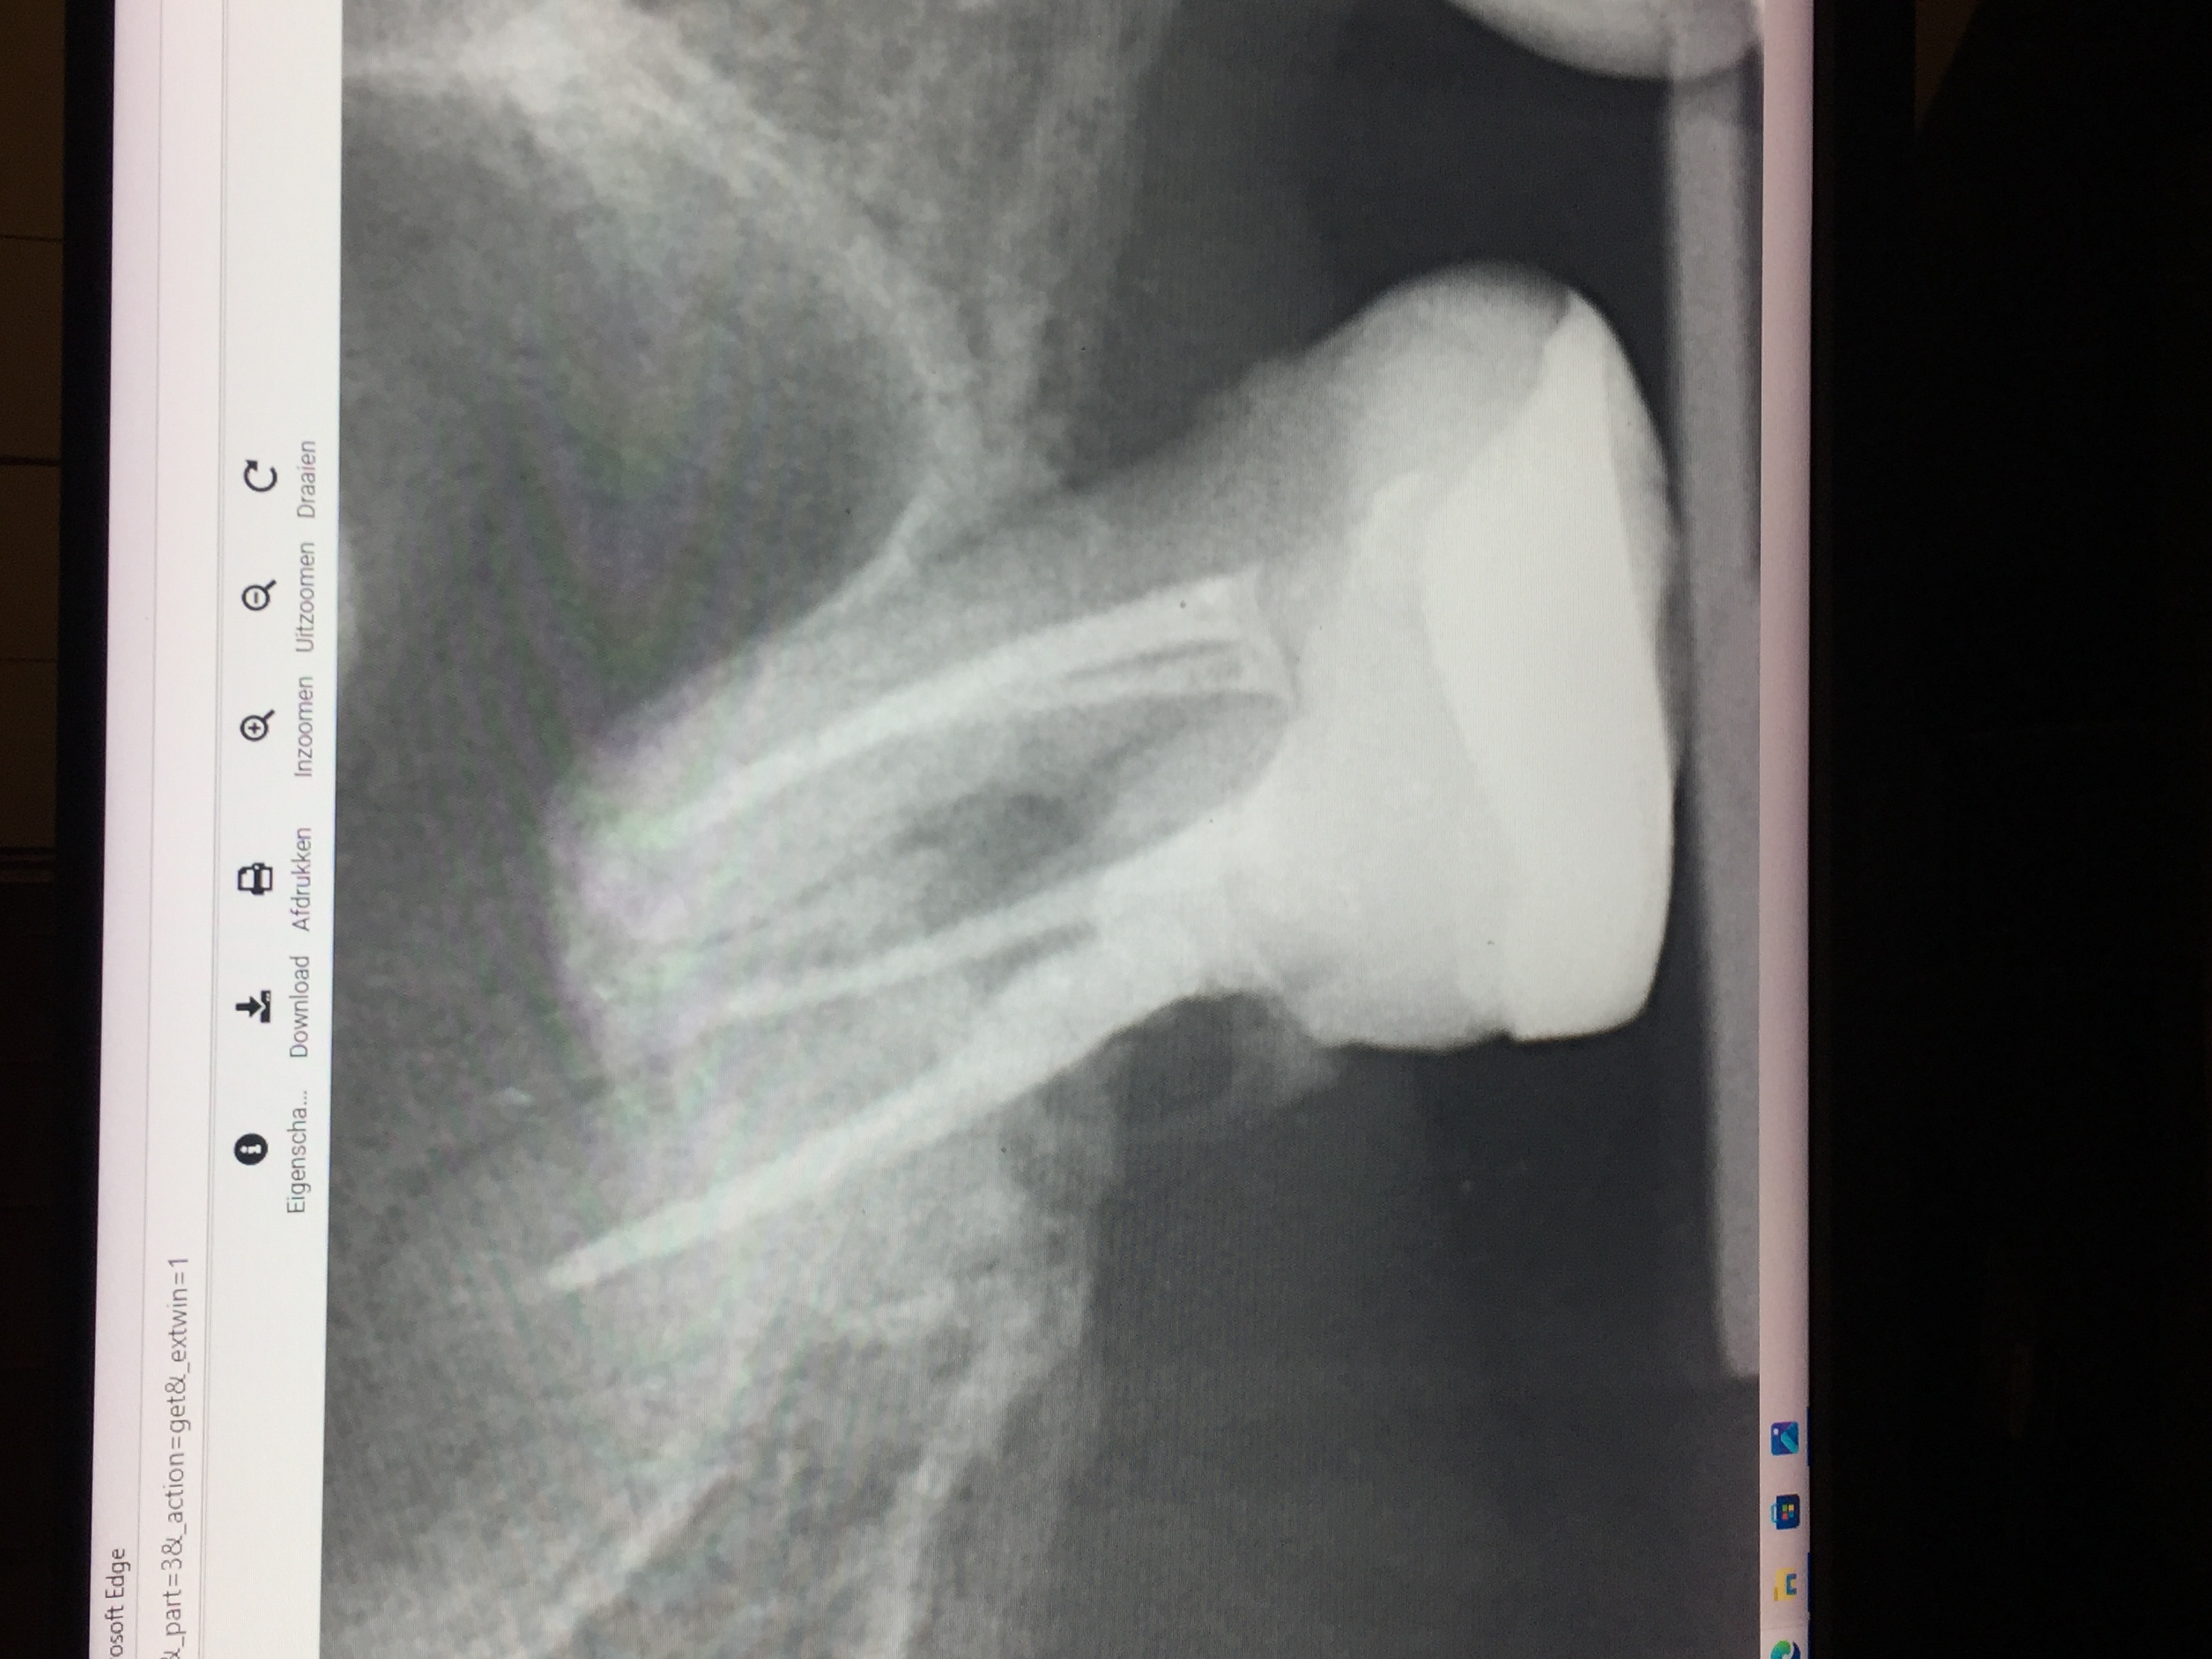

ik heb even een foto erbij voor Tandarts Richard .wat kunt u concluderen aan de hand van deze foto?

Attach

Tandarts_Richa…

idd lijkt op wortel resorptie. Element is helaas verloren. Oppassen voor mogelijke Antrum perforatie ( verbinding met neusholte) met verwijderen aangezien bot erg dun lijkt. Weet niet hoe de rest v h gebit eruit ziet.. maar nadenken over vervanging.